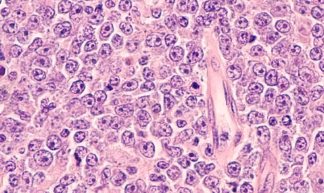

**림프종(Lymphoma)**은 림프계에 생기는 혈액암의 일종으로, 면역세포인 림프구가 비정상적으로 증식하며 발생합니다.

✅ 조직검사 – 림프절을 떼어내 정밀 조직검사 (가장 중요한 진단법)